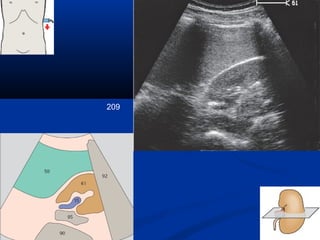

209